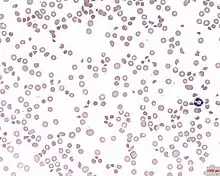

| Blood under a microscope showing thrombocytopenia | |